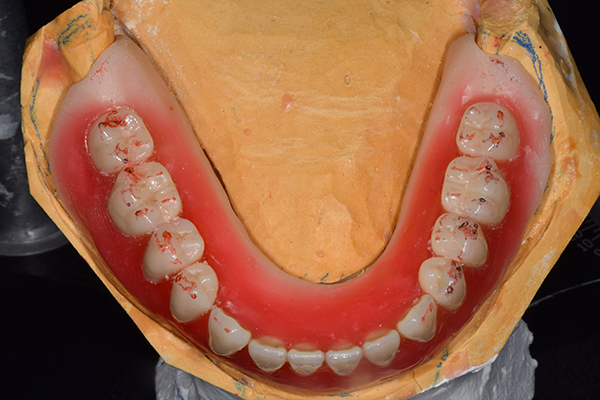

8.患者様のお口に入れて修正

この写真は、実際にお口の中にいれてみて、噛み合わせのチェックを行い、調整したものになります。 上下の入れ歯で青い点、赤い点がはっきりあり、これはしっかり奥歯で噛めるというサインになります。 また、入れ歯自体の大きさや、違和感が強くないか、お顔と調和しているか、唇との関係などをみていきます。もし、ここで大きな修正が発生する場合はもう一度お時間をもらって次回再度確認させて頂きます。 これで修正が終わったら、その模型を技工所に送り、入れ歯を完成させてもらいます。